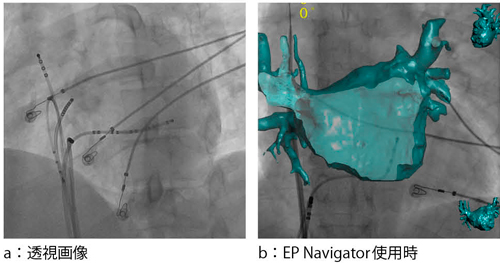

カテーテルアブレーションは,頻脈性不整脈に対する根治治療として用いられている。その中でも,左心房の肺静脈をアイソレーションする手技は,確立された治療として認知されている。しかし,手技中の透視画像上にはカテーテル等のデバイスしか映っておらず,左心房との正確な解剖学的位置関係を把握しながらカテーテル操作を行うことは困難であった(図4 a)。これをサポートするアプリケーションが“EP Navigator”である。

EP Navigatorは,左心房の3D画像を透視画像上に重ね合わせる3Dロードマップ機能である。これにより術者は,カテーテルと左心房の解剖学的位置をリアルタイムに確認できる。抽出された左心房の3D画像は,アームの動き,SID,天板の位置変更にもリアルタイムに追従する。さらに,内腔表示機能により,カテーテルの先端が肺静脈のどの位置にあるかをより正確に把握できる(図4 b)。左心房の3D画像の選択は 2通りあり,1つは心臓CT画像によるもので,もう1つは,血管撮影装置による回転撮影(3D-ATG)による抽出である。3D-ATGは,1回の回転撮影で左心房の3D画像を再構成する。再構成された左心房は,心臓CT検査による抽出とほぼ同等のクオリティで,かつ,手技当日の左心房の形態を忠実に再現できる。術中に左心房の解剖学的位置をより正確に把握でき,アブレーションにおける新たなイメージガイダンスとして期待されている。

図4 EP Navigator EP Navigatorによる左心房の内腔表示により,カテーテル位置の正確な把握が可能となる。

EP Navigatorによる左心房の内腔表示により,カテーテル位置の正確な把握が可能となる。